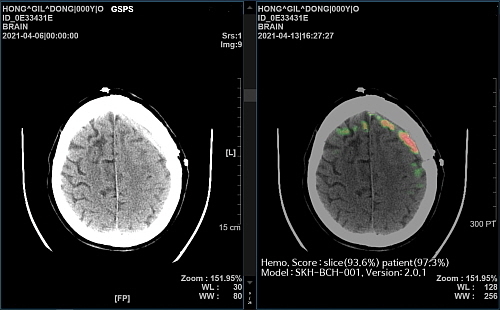

이어 17일에는 ‘2022 아소시오 테크 엑셀런스 어워즈’에서 자사가 개발한 AI 뇌출혈 영상 의료 솔루션인 ‘메디컬 인사이트 플러스 뇌출혈(Medical Insight+ Brain Hemorrhage)’이‘헬스테크 어워드(HealthTech Award)’를 수상했다고 밝혔다.

우수한 기술 역량을 기반으로 한 뇌출혈 영상 판독 인공지능 솔루션을 다수 의료기관에 적용해 빠르고 정확한 환자 진료를 도왔으며, 의료 리소스가 부족한 비수도권 보건의료원 지원을 통해 의료 취약지역 해소에도 노력했다는 점을 높이 평가받았다.

현재 메디컬 인사이트 플러스 뇌출혈은 서울, 경기, 인천, 대구 등 전국 권역별 주요 종합병원 30여개 의료기관에 공급됐으며, 강원도 평창군, 전라북도 무주군, 경상북도 울릉군 보건의료원 등 공공의료기관에도 공급돼 의료 취약지역 내 응급의료를 지원하고 있다.